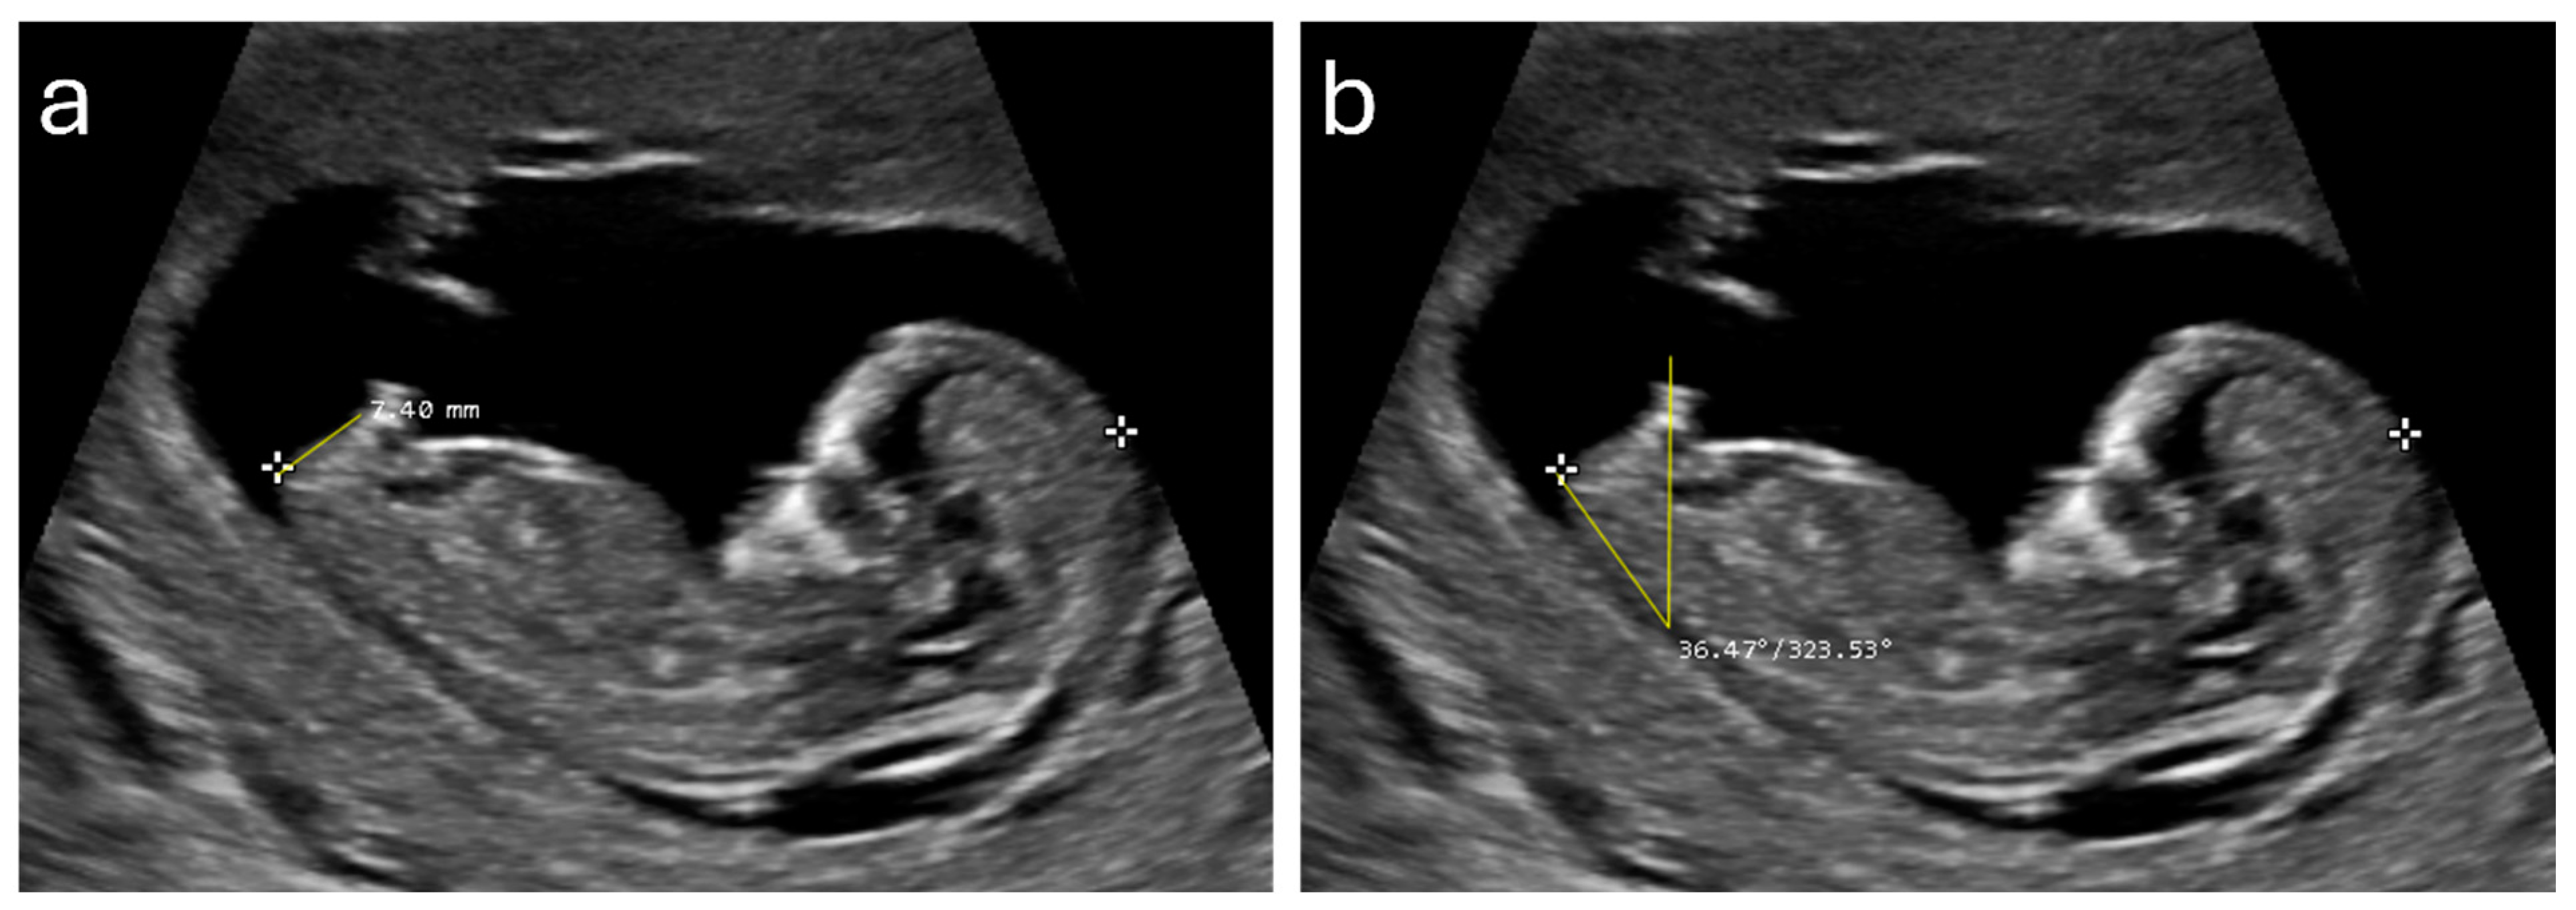

| AGD (mm) | 7.16 (1.40) | 3.0–10.77 | 4.42 (1.05) | 2.43–9.0 | 6.07 (1.85) | 2.43–10.77 |

| GTA (degree) | 35.90 (6.20) | 8.13–54.0 | 21.57 (7.29) | 7.32–39.0 | 30.21 (9.67) | 7.32–54.0 |